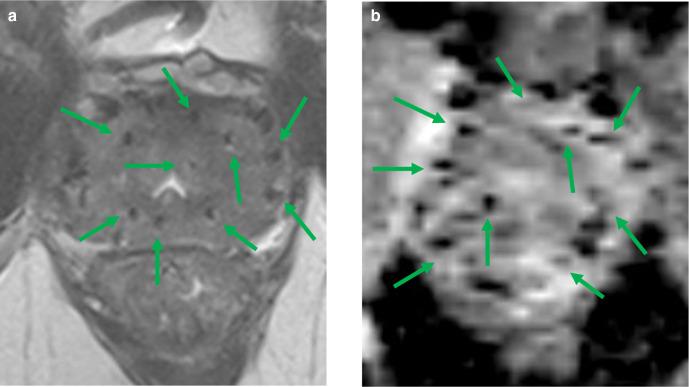

微创磁共振影像引导下的前列腺介入治疗。

Minimally invasive magnetic resonance image-guided prostate interventions.

全腺体前列腺癌治疗,包括根治性前列腺切除术或放射治疗,具有高度有效性,但也对生活质量产生重大影响,并可能对低危到中危疾病的男性造成过度治疗。微创治疗策略是新兴技术。不同的能源被用于靶向治疗,以减少治疗相关的并发症和发病率。成像在靶向和监测治疗方法中发挥着重要作用,以保留前列腺组织的部分。多参数磁共振成像(mpMRI)由于具有多平面和实时解剖成像功能,在图像引导介入中得到广泛应用,同时提供了更高的治疗准确性。本综述评估了使用 MRI 或 MRI/经直肠超声(MRI/TRUS)融合引导成像的现有图像引导前列腺癌治疗选择。讨论的微创图像引导前列腺介入治疗可被视为(复发性)前列腺癌患者安全可行的部分腺体消融。然而,大多数关注微创前列腺癌治疗的研究仅报告了研究的早期阶段,仍然需要后续的高级别证据。确保最受益的患者安全和适当的应用,并由具有相关培训的医生进行应用,已成为微创前列腺癌治疗的主要挑战。